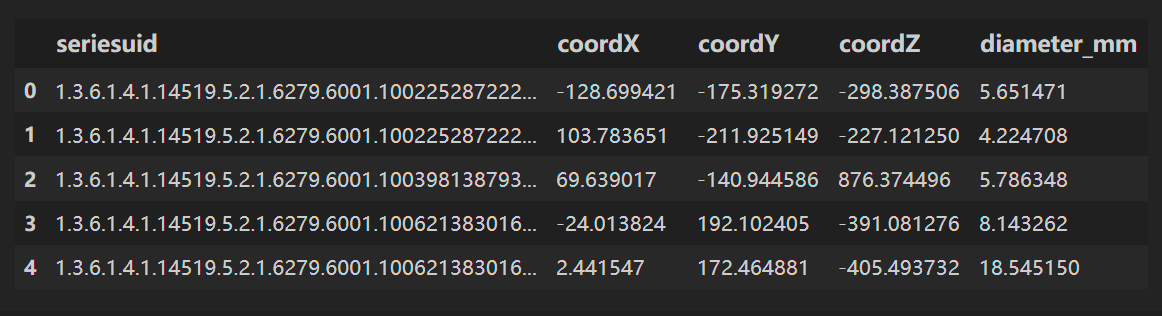

读取 annotations.csv

annotations.csv⽂件包含⼀些已标注为实际结节的候选者的信息,我们对diameter_mm(结节直径)列所代表的信息特别感兴趣。

annotations = pd.read_csv(path+'annotations.csv')

annotations.head()